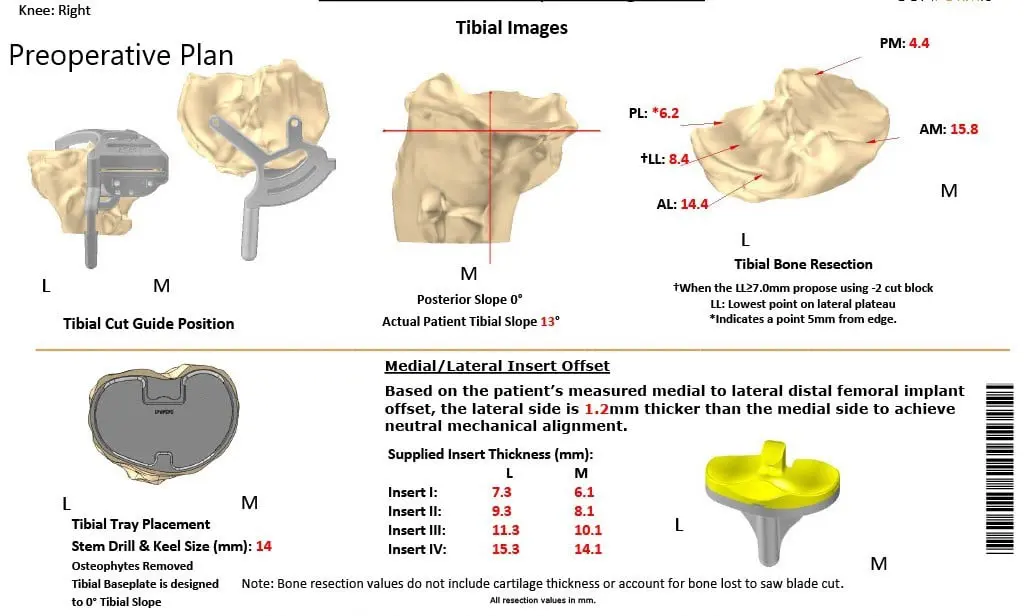

A preoperative CT scan obtained a few weeks prior to the procedure. The data was used to assess the patient’s unique anatomy and biomechanics. Customized unique patient-specific implants were made. Disposable bone cutting guides were 3D constructed to match the patient’s anatomy. A preoperative plan was formulated to guide the surgery.

Complete Orthopedics patient-specific surgical plan for a custom right total knee replacement in a 55-year-old female with Prior ACL Reconstruction.

Complete Orthopedics patient specific surgical plan for a custom right total knee replacement in a 55-year-old female with prior ACL Reconstruction (scan 2)